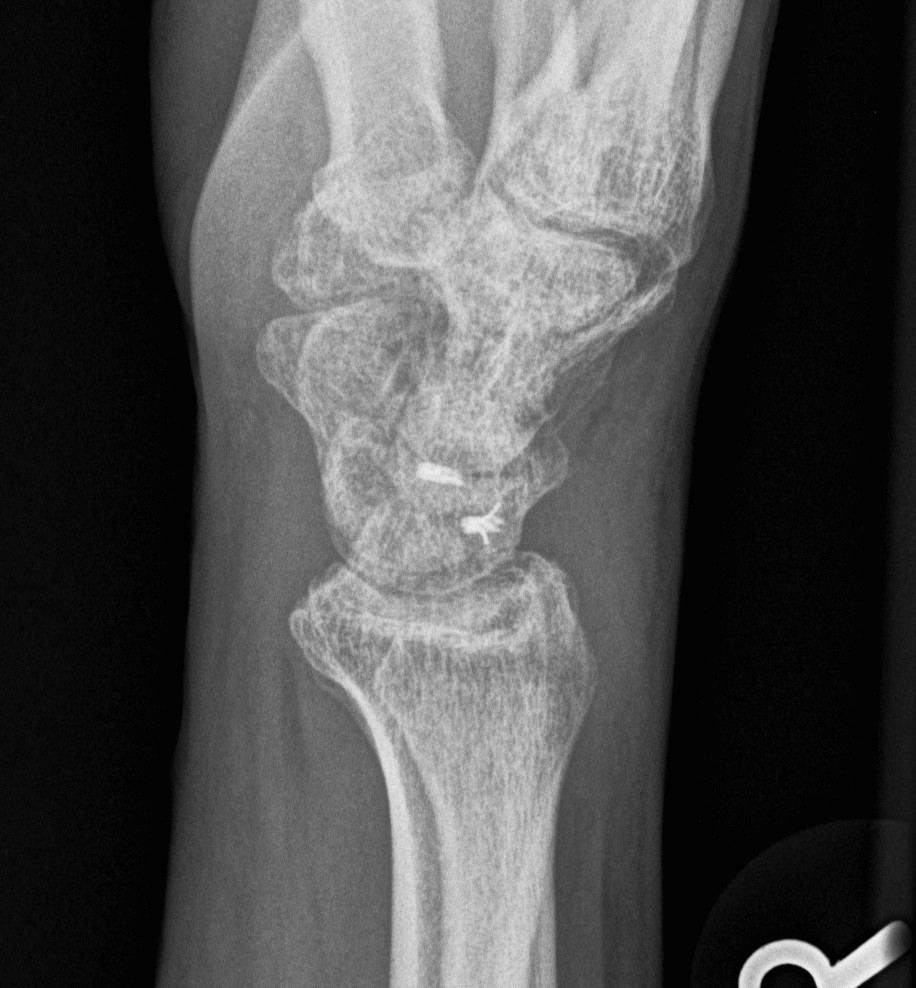

Lateral

Palmarflexion of scaphoid

Dorsiflexion of lunate

Increased scapholunate angle

- > 70o

- usually 30 - 60o

Increased luno-capitate angle

- normally < 10o

Increased radio-lunate angle

- lunate extended > 10o